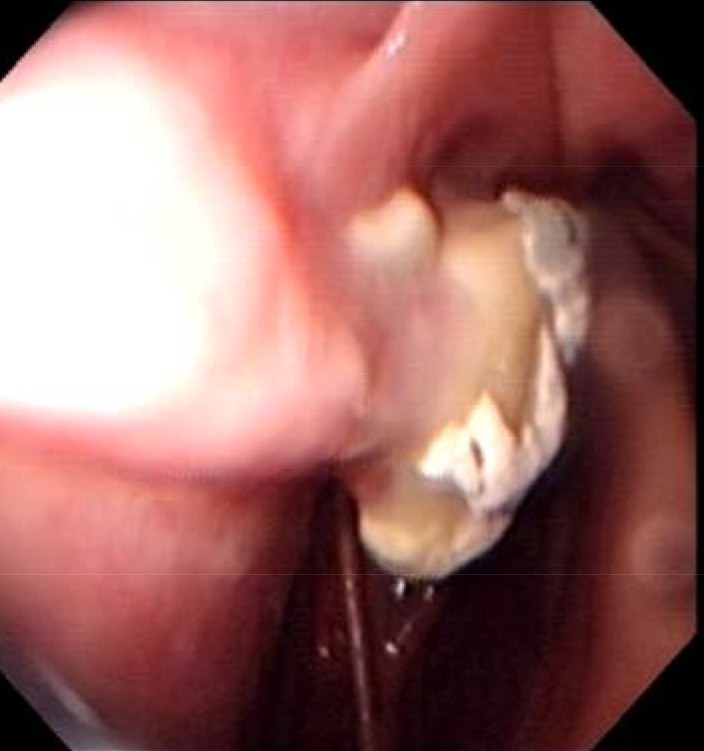

les poches après les 10 jours en clinique

et les poches 5 semaines plus tard

Merci pour l'illustration, ça donne un vraie idée de ce qui se passe

Ton endoscopie est vraiment très illustrative. Je vais essayer d'avoir celle de ma juju.